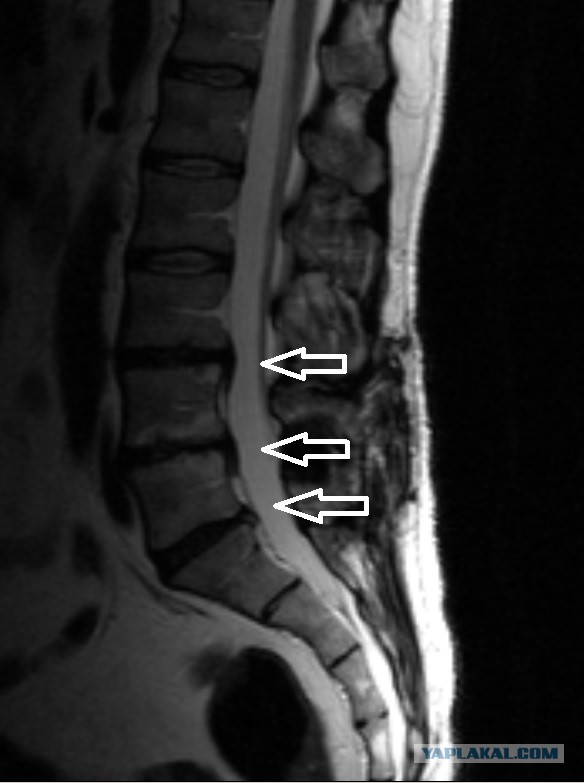

Я не хотел делать МРТ: меньше знаешь - крепче спишь, но пол-года назад жена заставила сделать. В итоге, на данный момент имеем 3 грыжи различных размеров, в том числе и там, где её ранее удалили. К Врачам претензий нет, свою работу они сделали ювелирно и высококлассно, как говорили другие нейрохирурги, которые видели МРТ после операции.

Тёмное пятно под средней стрелкой - это имплант.

К врачу конечно стоит, но судя по снимку, грыжи в поясничном отделе, там спинного мозга нет и врядли вот так сразу парализует. Если бы грыжа была в верхних отделах позвоночника и сдавливался непосредственно спинной мозг то это да, очень серьезно. Но осложнения и сопутствующие возникающие проблемы могут очень портить жизнь.

На снимке МРТ сделал пояснения что где. Спинной мозг выглядит светлой лентой, идущей справа от позвонков.

Дальше, если нагрузки велики, хрящевое кольцо трескается, лопается и через разрыв, как зубная паста из тюбика, выдавливается тело диска. При этом сдавливается спинной мозг, нарушается его кровоснабжение, ощущаются онемение, прострелы и прочие "радости".